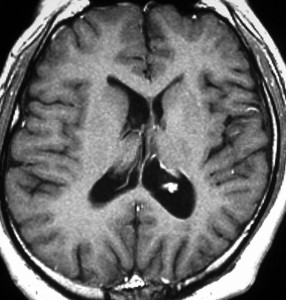

結節性硬化症 TSに見られる多発性上衣下結節 subependymal nodules

32歳で初めて睡眠時てんかん発症した患者さんのものです。側脳室壁だけに無数の上衣下結節がありますが,治療の必要はありません。SEGAではありません。